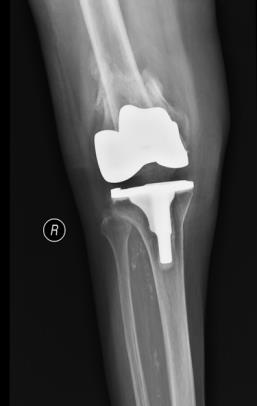

该科擅长对膝关节严重创伤(包括股骨远端骨折、髌骨骨折、胫骨平台骨折等)、膝骨关节炎阶梯化治疗、保膝治疗、膝关节微创单髁置换术、全膝关节置换术、膝关节翻修术具有丰富的临床诊疗经验,追求微创、无痛、快速康复。